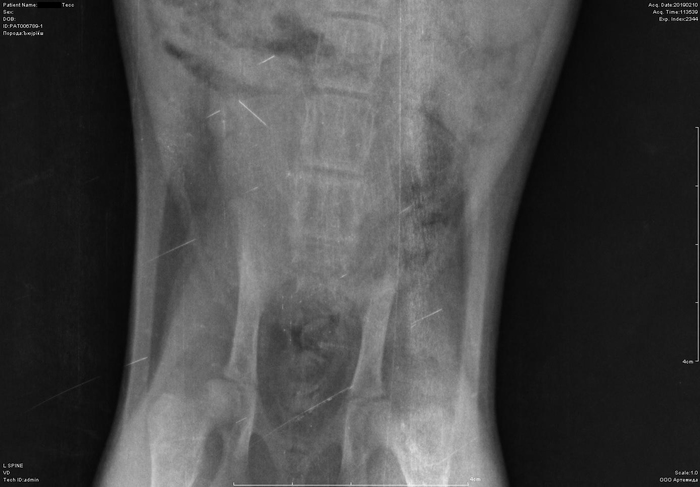

Рентген котенка

Добрый день. Котенок рожден 5 ноября 2018 года, девочка, не привита. Проглистована. Неожиданно в один момент стала припадать на задние ноги. Как бы бережет их и старается не прыгать лишний раз. Свозили два дня назад к ветеринару - всю её прощупал, говорит переломов нет, вывихов тоже. Сделали блокаду ближе в крестцу новокаина, чтобы снять симптомы. Прописал кальций в таблетках Ексел. Сейчас всё примерно так же - лапки задние бережет, но стала по активнее. Прошу специалистов, если такие тут бывают, оценить снимки, т.к. врач ещё кое-что сказал и хотелось бы услышать ваше мнение. Скан расшифровки и д/з потом приложу.